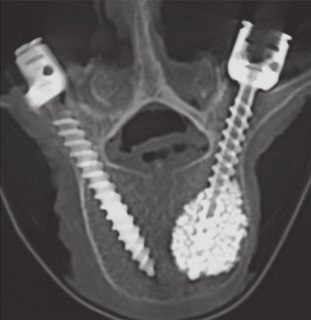

• FAQ: FMax-G for augmentation, the new cutoff

Cook, 2004: Augmentation gives up to 250% more strength [2], with a leakage risk for each screw. If underused, a sole bad anchorage may cause material failure. Global indicators like T-Score are poor predictors.

The new paradigm: Assessing the augmentation benefit/risk balance with Fmax-G, the Pedicle-Specific Predictor.